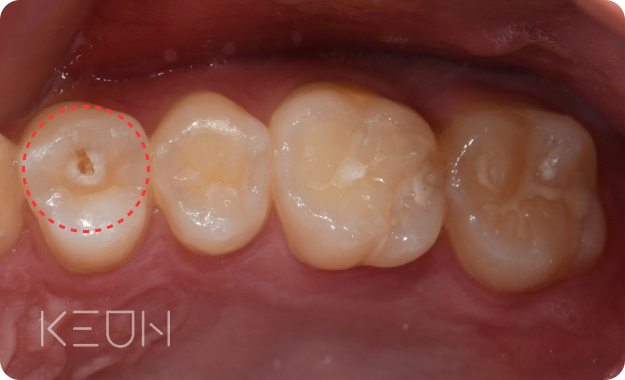

레진치료

충치를 제거하고 난 후 손실된 부위에 레진을 바로 메우는 방법

- Before

로그인 후 확인 하실 수 있습니다!- After